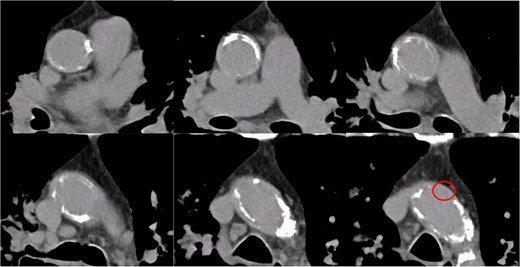

A 77-year-old man with chronic kidney disease was admitted to another hospital with heart failure and was diagnosed with IHD and triple vessel disease (Fig. 1). On examination, femoral pulses were absent, and angiography revealed occlusion of the abdominal aorta below the renal arteries. Therefore, he was transferred to our hospital for further management. Heart failure was stabilized with medical therapy, and semi-urgent surgery was planned. Because he had no symptoms in the lower extremities, elective performance of revascularization of the lower limbs was scheduled. The ITAs served as important collateral vessels to the lower limbs (Fig. 2); therefore, their use as grafts was considered a risk factor for lower limb ischemia. Transthoracic echocardiography revealed impaired systolic function with an ejection fraction of 42%, whereas contrast-enhanced computed tomography (CT) demonstrated diffuse calcification of the ascending aorta (porcelain aorta). However, an area near the origin of the brachiocephalic artery was considered suitable for arterial cannulation, and a proximal site above the fat band was identified as appropriate for saphenous vein graft (SVG) anastomosis (Fig. 3). Based on these findings, an on-pump total venous CABG strategy was selected, and surgery was performed on the second day after transfer.

Preoperative contrast-enhanced CT of the ascending aorta. The ascending aorta is diffusely calcified. A region near the origin of the brachiocephalic artery is considered suitable for arterial cannulation. A proximal site above the fat band is also identified as appropriate for SVG anastomosis.